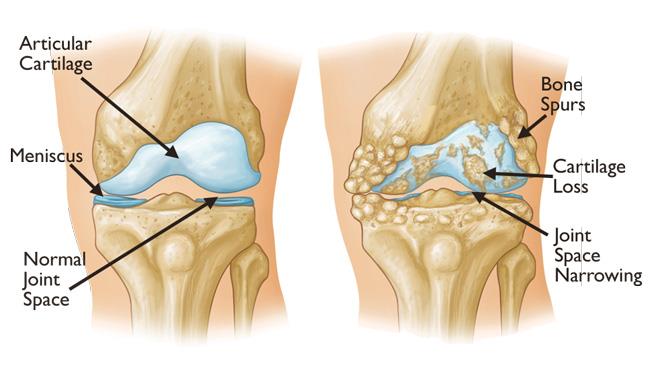

Knee arthritis is a condition where the cartilage in the knee joint gradually wears away, leading to pain, stiffness, swelling, and reduced mobility. It can affect one or both knees and is more common in older adults, though younger people can develop it due to injury or genetic factors.

These factors can lead to inflammation, breakdown of cartilage, and changes in the underlying bone.

- X-rays to detect joint space narrowing, bone spurs, or changes in bone structure

- MRI scans to assess cartilage and soft tissue